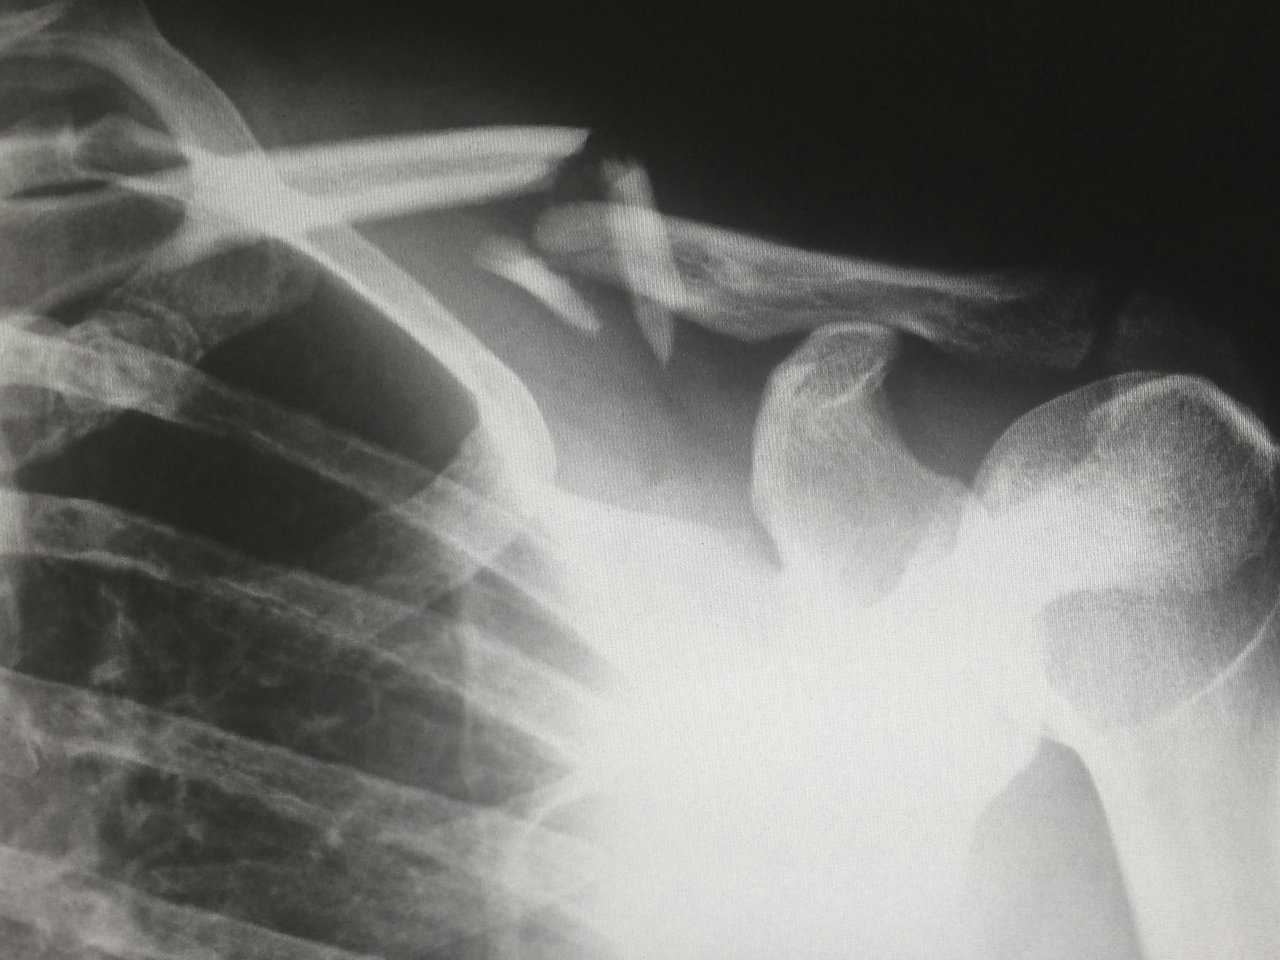

Auf dem Gebiet der Orthopädie liegen die Behandlungsschwerpunkte unserer Kliniken bei folgenden Indikationen: Operativer Gelenkersatz (Endoprothetik); Z.n.OP eines Bandscheibenvorfalls, einer Spinalkanalstenose oder der Wirbelsäule; Degenerative Erkrankungen des Bewegungsapparates; Konservative Frakturbehandlungen (z.B. Beckenfraktur); Osteosynthese von Frakturen, OP bei Bandverletzungen, Traumabehandlung nach Unfällen und Verletzungen.